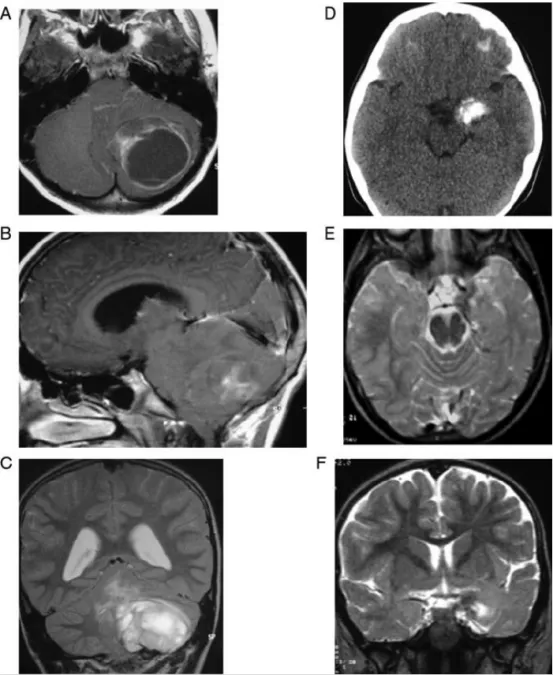

脑室内肿瘤是神经内镜手术的理想适应证,这类病变可经脑室系统自然腔道直达,内镜操作路径短且直接;又因肿瘤常阻塞脑脊液循环通路,引起脑室代偿性扩张,为内镜提供了充足的操作空间...